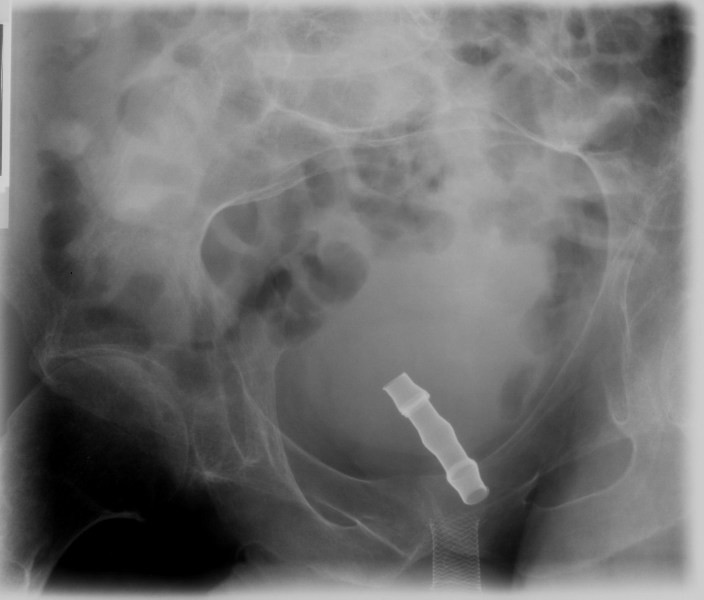

Figure 3From: Lessons we learn from review of urological procedures performed during three decades in a spinal cord injury patient: a case reportCystogram (10 September 1993) shows Urocoil stent has migrated proximally into urinary bladder.Back to article page